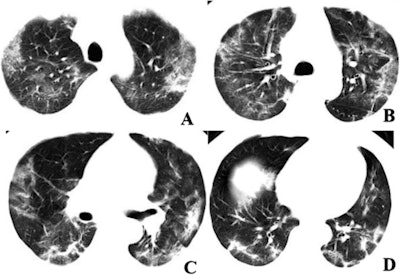

Chest CT scans of a 60-year-old male with COVID-19 showing multifocal ground-glass opacities and mixed consolidation in the peripheral area of both lungs. DNA tests returned negative for 2019-nCoV until the eight day after presentation. Image courtesy of the RSNA.After examining the data, the researchers found that the combination of CT and DNA analysis was able to confirm a diagnosis of COVID-19 in the vast majority of the patients (93%). However, in five of the patients (3%), CT scans indicated COVID-19 despite the disease being only weakly positive on initial DNA analysis for one case and entirely ruled out for the other cases.

In the case of one 29-year-old male, the initial DNA test was negative for 2019-nCoV and so was the follow-up DNA test performed several days later. His CT scans showed multifocal mixed ground-glass opacities and parenchymal consolidation involving the subpleural regions of both lungs. The patient was not admitted to the hospital for isolated treatment until a third DNA test based on a sample collected eight days after initial presentation turned out positive for the virus.